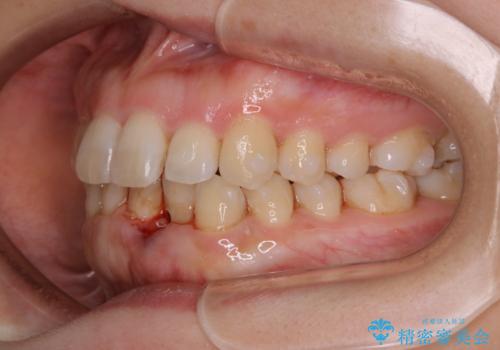

インビザライン・ライトでの抜歯矯正治療 (スリーインサイザー仕上げ)

- 上下の前歯のがたつきが気になるとのことで来院されました。最短治療とインビザラインでの矯正治療をご希望されました。

前歯のがたつきを無くすためには、スペースを確保する必要があります。上の前歯のがたつきは軽度ながたつきのため、歯と歯の間を研磨をして、そのスペースを使い並べていきます。下の前歯は、1本前歯を抜いて研磨せずに、その抜歯したスペースを使い並べることになりました。

インビザライン・ライトにて矯正治療を行うことになりました。

下の前歯は、スリーインサイザー仕上げと言って、通常前歯は4本ありますが(犬歯はいれていない)、そのどれか1本を抜歯して前歯を3本にして矯正治療を行うことを言います。また、先天的に歯の本数が少ない方もいますので、矯正治療を行っていなくても元々スリーインサイザーの方もいます。